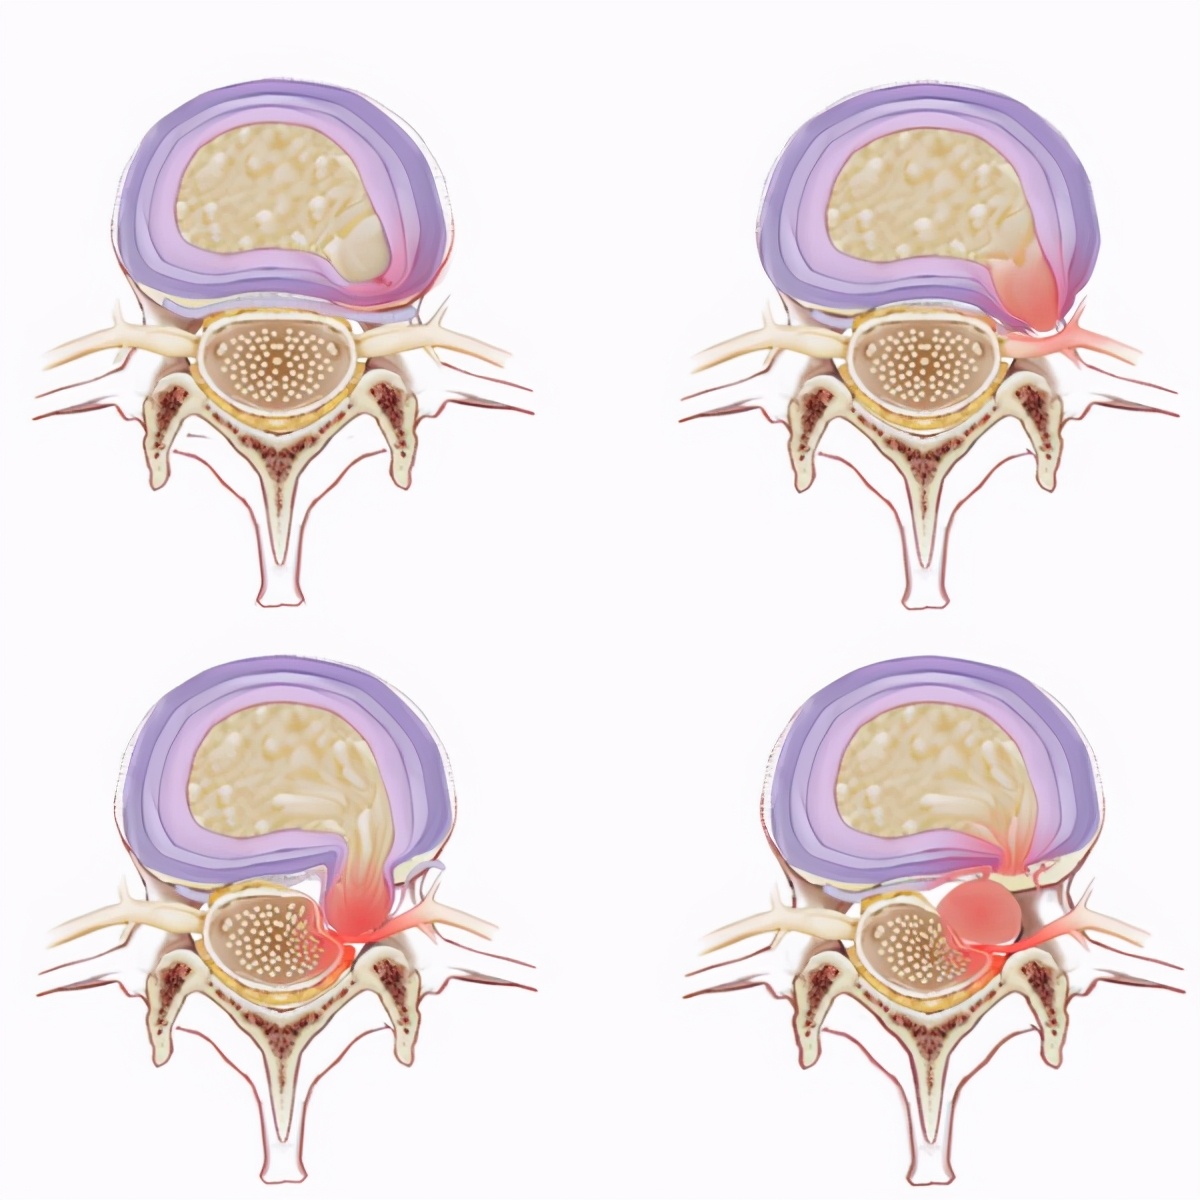

腰椎间盘突出有四种形式。

1. 腰椎间盘膨出:有点像包子被拍成馅饼了,椎间盘高度降低,这是一种典型的退变,髓核水分丢失,纤维环弹性降低。腰椎间盘膨出常常导致神经通道的狭窄。

2. 腰椎间盘突出:纤维环并没有完全破裂,由于髓核反复挤压,再加上椎间盘后面的后纵韧带的限制,椎间盘向侧方突出,常常挤压神经根。

3. 腰椎间盘脱出:纤维环完全破裂,髓核顺着破裂的纤维环突出到椎管。就像馅饼皮破了,馅露到外面。

4. 游离性椎间盘脱出:脱出的髓核掉到椎管里。